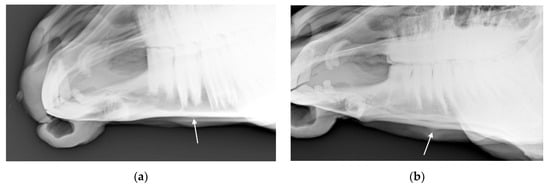

Figure 5. Radiographs showing the nasal bones of a horse in which radiologists (n = 2) agreed there was bone thinning that was: (a) typical of affected horses and (b) moderate.